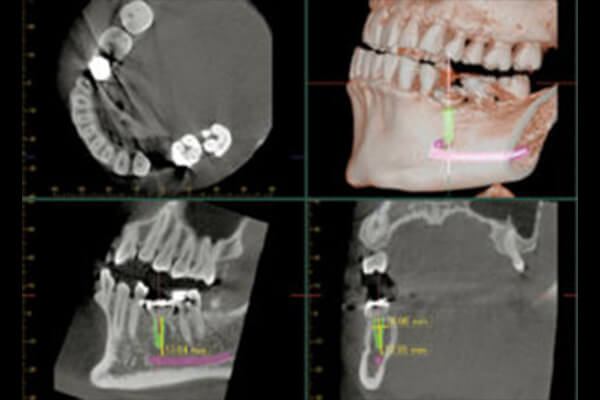

●解析力:3次元での画像解析が可能になる

●可視性:通常のレントゲンでは見れない領域まで見る事が出来る

インプラント治療において最も需要なことは、事前の正確な診断と計画を行うことです。診断が不十分だったために…計画が行き届いていなかったために…失敗に終わってしまうケースも少なくありません。

が、当院では患者様に安心してインプラント治療を受けて頂くため、患者様のお一人お一人の歯や骨の状態をしっかりと把握した上で的確な診断と計画を行います。より安全で確実なインプラント治療を行うために、CT(Computed Tomography)撮影による診断が不可欠と考えております。

当クリニックでは、インプラント治療を希望される患者様には、必ずCT撮影を受けて頂くことになります。インプラント治療の安全性を一層高めるために必要なことですので、ご了解いただけますと幸いです。

骨の厚みや量を診断した上で

インプラントの埋入計画が可能

通常のデジタルレントゲンでは

解析が難しい範囲も分析可能